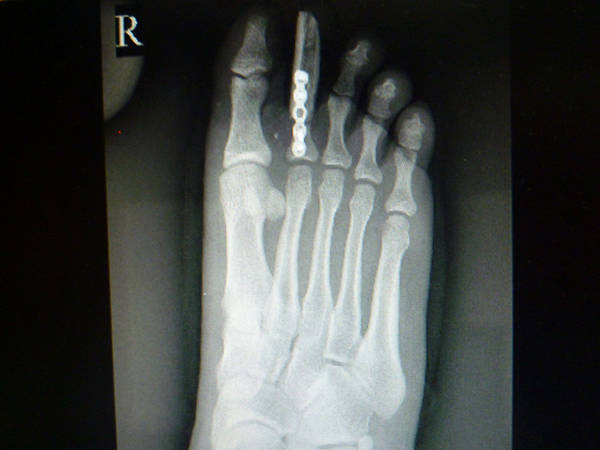

[手指再造] 拇再造术后供区的另一种修复(12.23随访照片来了)

池老师手术做的确实漂亮。有个疑问:既然食指切除了,为何不直接把废弃食指指骨连同食指皮瓣修复再造供区,这样就不用取游离腓骨皮瓣了

1.jpg 2.jpg 3.jpg 4.jpg 5.jpg 6.jpg 7.jpg 8.jpg 9.jpg 10.jpg 11.jpg 12.jpg 13.jpg

功能和外观都很好,学习了,池主任的病人应该感到幸运和幸福